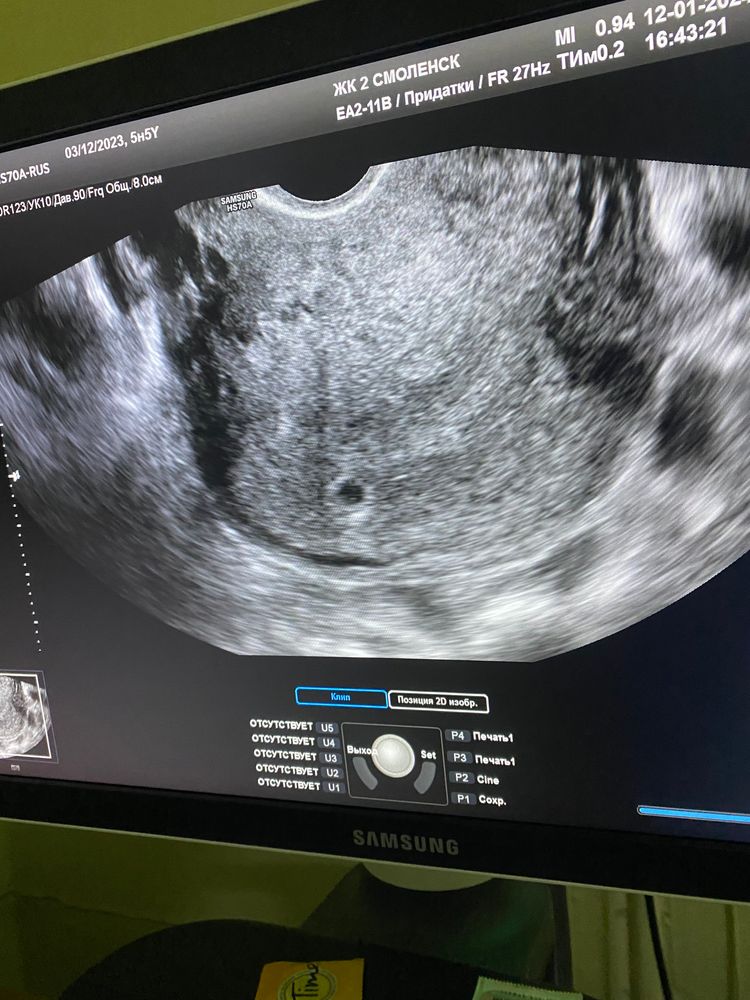

4 эмбриональные недели узи

4 эмбриональные недели узи 148 фотографий